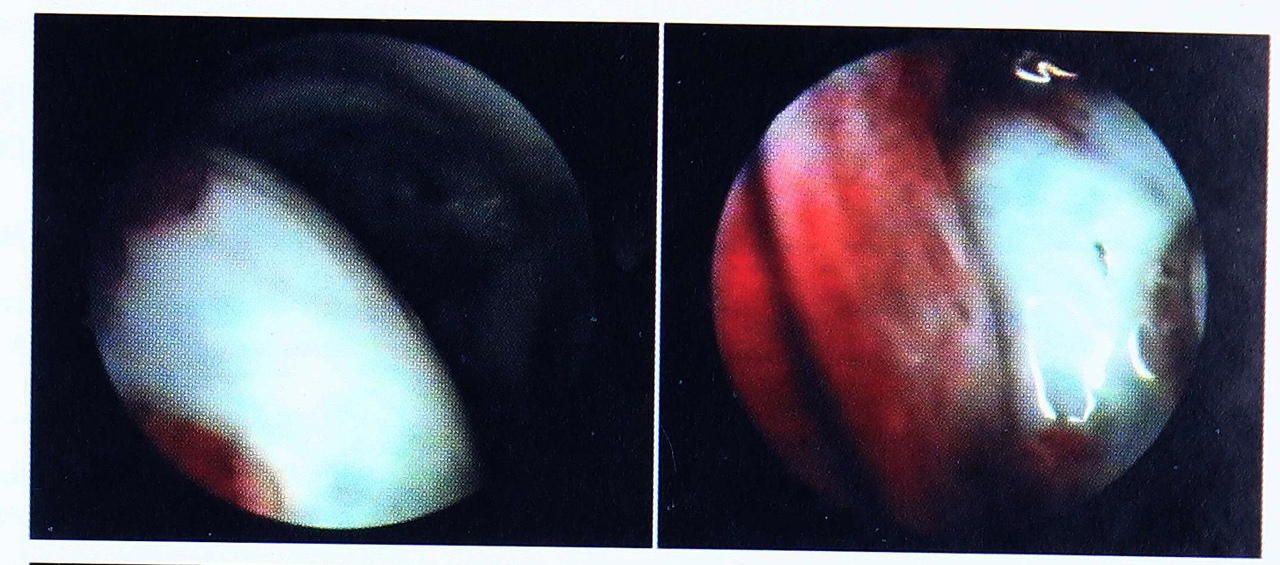

Рис. 4. Артроскопическая картина трансхондрального перелома головки бедренной кости (больной А.).

При клиническом обследовании заподозрена внутрисуставная патология правого тазобедренного сустава, однако на рентгенограммах и КТ признаков травматического повреждения костных структур не выявлено. Учитывая это, а также неэффективность проводившегося ранее консервативного лечения, решено прибегнуть к артроскопическому вмешательству. Первым этапом наложена демпферная система разгрузки на правый тазобедренный сустав. Вторым этапом произведена артроскопия (рис. 4). При ревизии сустава обнаружены дефект суставного хряща размером 3,5x3,0 см на передневерхней поверхности головки бедренной кости, свободные фрагменты хрящевой плотности в полости сустава; круглая связка без изменений, хорошо инъецирована сосудами. Выявленная картина расценена как посттравматический трансхондральный перелом головки бедренной кости. Внутрисуставные тела удалены, произведено шейвирование зоны поврежденного суставного хряща, сустав обильно промыт физиологическим раствором.